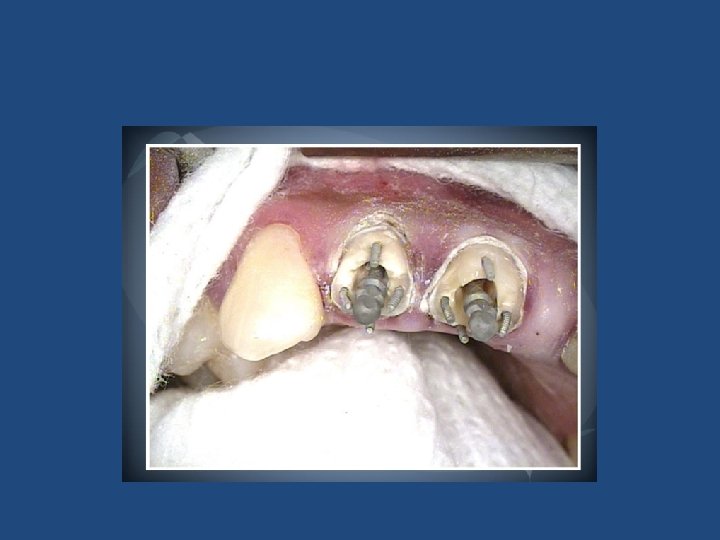

Endodontik Tedavili Dişler • • • Amalgam veya Kompozit. Dolgu Dentin Pini, Oluk veya Yuva Uygulamaları Prefabrike Metal Kanal Çivisi Fiber Post Döküm Post-Core CAD-CAM ile Üretilmiş Postlar